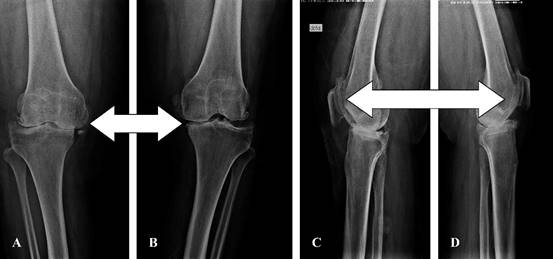

Radiografías previas a cirugía (Figura 6).

Figura 6: Radiografías anteroposterior y lateral de paciente con gonartrosis grado IV (flechas blancas). A-B) Radiografía anteroposterior de ambas rodillas: se observa artrosis en compartimento medial y lateral. C-D) Radiografía lateral de ambas rodillas: se observa artrosis patelofemoral.